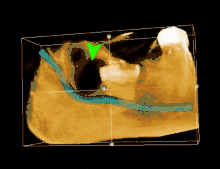

| 3D CT of an impacted wisdom tooth adjacent the inferior alveolar nerve prior to removal of wisdom tooth | |